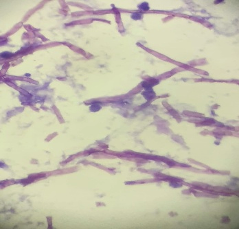

A 52 year old male was clinically diagnosed with a space-occupying lesion in the left parietal lobe of brain. Squash and other smears were made .3 images are shown, make you diagnosis and why?